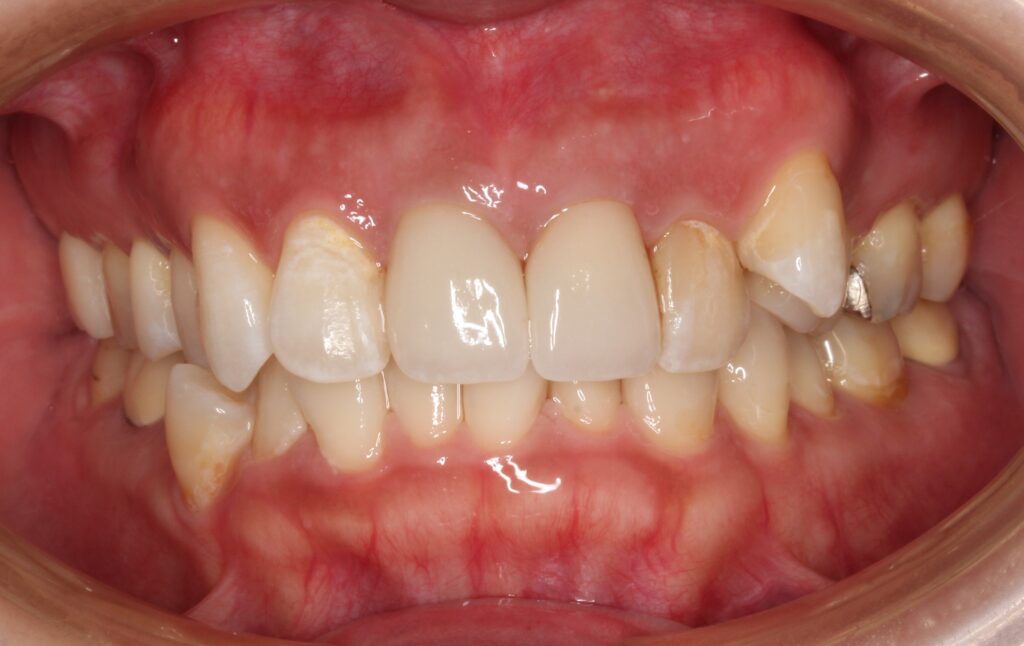

綺麗に歯がそろいました(^^)/

歯ぐきの黒い色もなくなり、全体的に明るく審美的に仕上がりました。

再度、最初のビフォーアフターの写真です。

患者さんの希望通りに治療が進み、見た目も改善して喜んでいただきました(*^-^*)